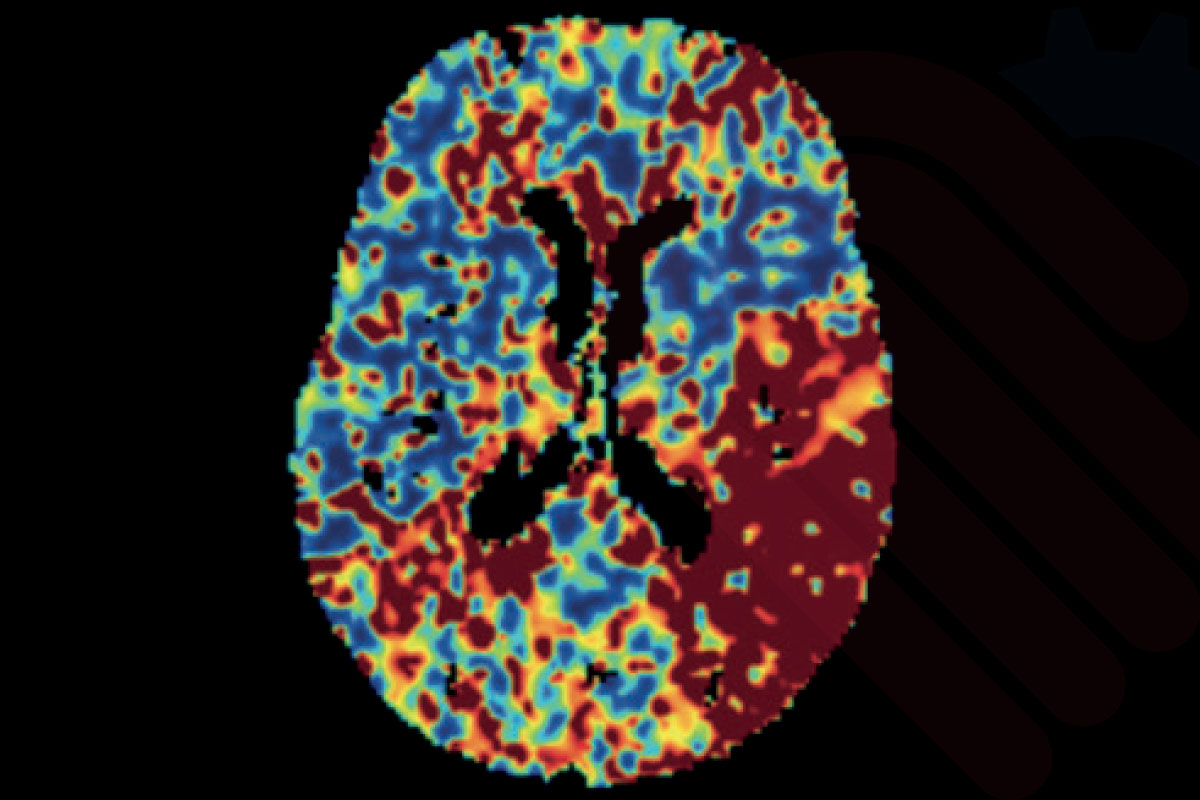

Cercare Medical Neurosuite Stroke yazılımının Gelişmiş SVD (Singular Value Decomposition) tabanlı perfüzyon analizleri, standart versiyona kıyasla daha ileri algoritmalar kullanarak doku perfüzyonunu hassas şekilde haritalandırır. Bu modül, beyin kan akımı (CBF), beyin kan hacmi (CBV), ortalama geçiş zamanı (MTT), zaman-gecikmesi (Tmax), maksimum yoğunluk projeksiyonu (MaxIP) ve tepe zamanı (TTP) parametrelerini yüksek doğrulukla hesaplar.

Gelişmiş SVD analizleri, özellikle iskemik penumbra (kurtarılabilir doku) ile infarkt çekirdeği (geri dönüşsüz doku) arasındaki ayrımı daha kesin yapabilmek için tasarlanmıştır. Klinik çalışmalar, bu yaklaşımın tedavi penceresinin uzatılmasına katkıda bulunduğunu ve uygun hasta seçimini %15–20 oranında daha isabetli hale getirdiğini göstermektedir*.

Ayrıca gelişmiş algoritmalar, standart SVD’de görülebilen gürültü ve artefaktları azaltarak hem CT hem de MR perfüzyon verilerinde daha temiz ve güvenilir haritalar üretir. Bu, tromboliz ve trombektomi gibi kritik tedavi kararlarının daha güvenle alınmasını sağlar.

Vasküler Model Tabanlı Perfüzyon Haritaları

Cercare Medical Neurosuite Stroke yazılımının gelişmiş paketinde yer alan vasküler model tabanlı perfüzyon haritaları, beynin damar yapısını hesaba katan sofistike algoritmalarla çalışır. Klasik SVD tabanlı yöntemlerin ötesine geçerek, kan akış dinamiklerini biyofiziksel modellerle birleştirir. Böylece beyin kan akımı (CBF), beyin kan hacmi (CBV), ortalama geçiş zamanı (MTT) ve gecikme parametresi (Tmax) gibi temel ölçümler, damar ağı simülasyonları üzerinden yeniden hesaplanarak daha yüksek doğruluk elde edilir.

Bu yaklaşım, özellikle yan akım dolaşımı (collateral circulation) bulunan inme hastalarında kritik öneme sahiptir. Klinik araştırmalar, vasküler model tabanlı analizlerin çekirdek infarkt alanı ile penumbra bölgesini ayırmada %15’e varan ek doğruluk sağladığını ve yanlış negatif oranını anlamlı şekilde azalttığını göstermektedir*. Böylece tedaviye uygun hasta seçiminde güvenilirlik artar, tedavi penceresi daha sağlıklı değerlendirilir.